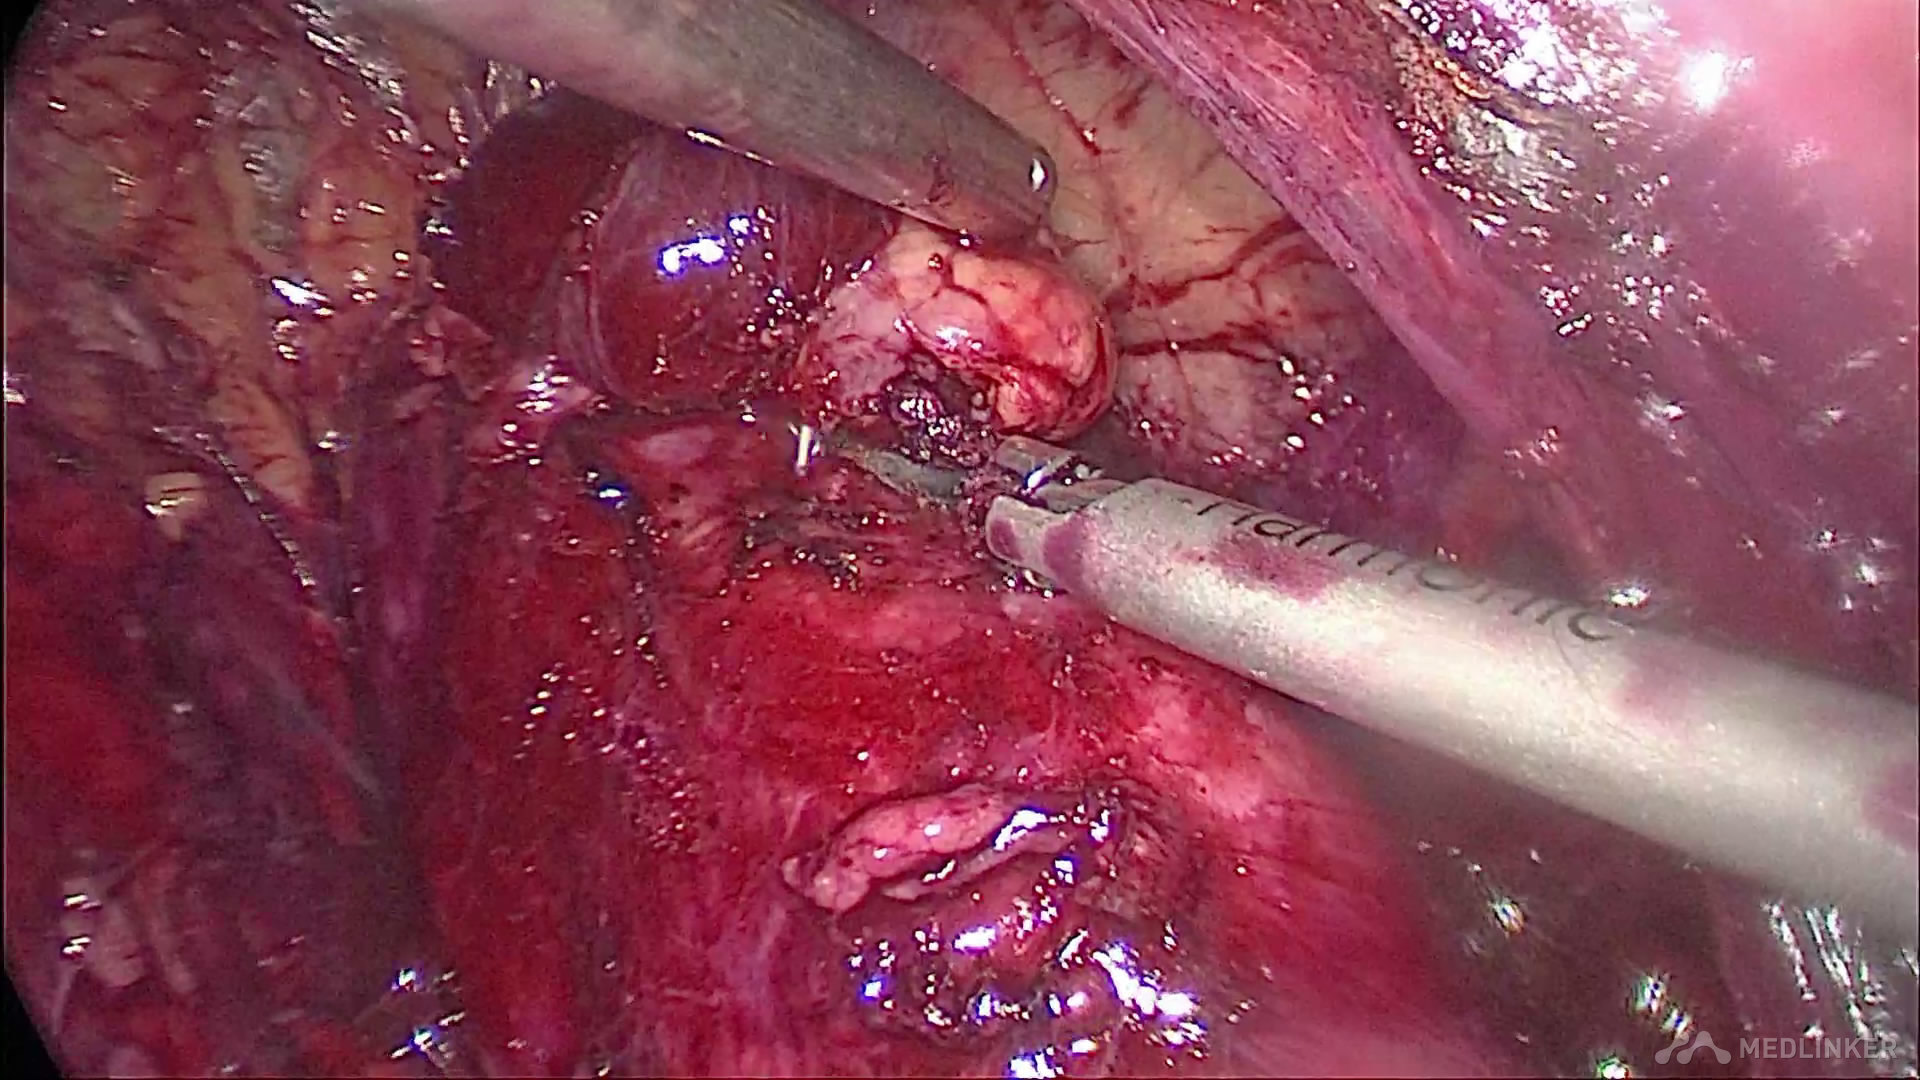

将深入肾实质的肿瘤切除,并仔细检查肾盂防止尿漏发生

夹闭肾段动脉,防止出血,并电凝肿瘤切面减少切缘阳性率的发生

可吸收线连续缝合残留肾脏创面,减少出血,促进肾功能的保护

缝合完毕后,开放右肾动脉,仔细检查创面渗血情况和缝合张力,必要时可加针缝合减少渗血